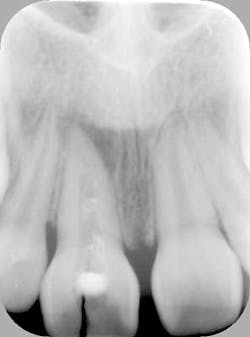

Fig. 2a: Post endodontic treated tooth prepared for decorination and root submersion for the purposes of preservation of alveolar bone prior to implant therapy